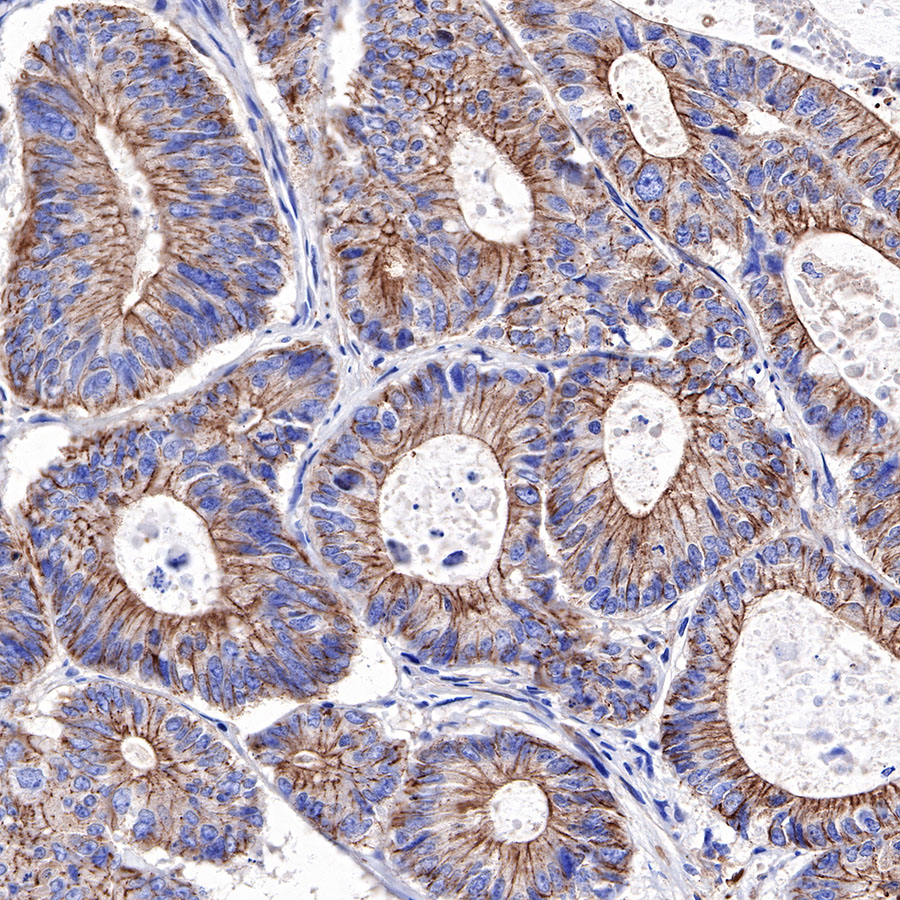

IHC shows positive staining in paraffin-embedded human colon cancer. Anti-α-Actinin-1 antibody was used at 1/2000 dilution, followed by a HRP Polymer for Mouse & Rabbit IgG (ready to use). Counterstained with hematoxylin. Heat mediated antigen retrieval with Tris/EDTA buffer pH9.0 was performed before commencing with IHC staining protocol.